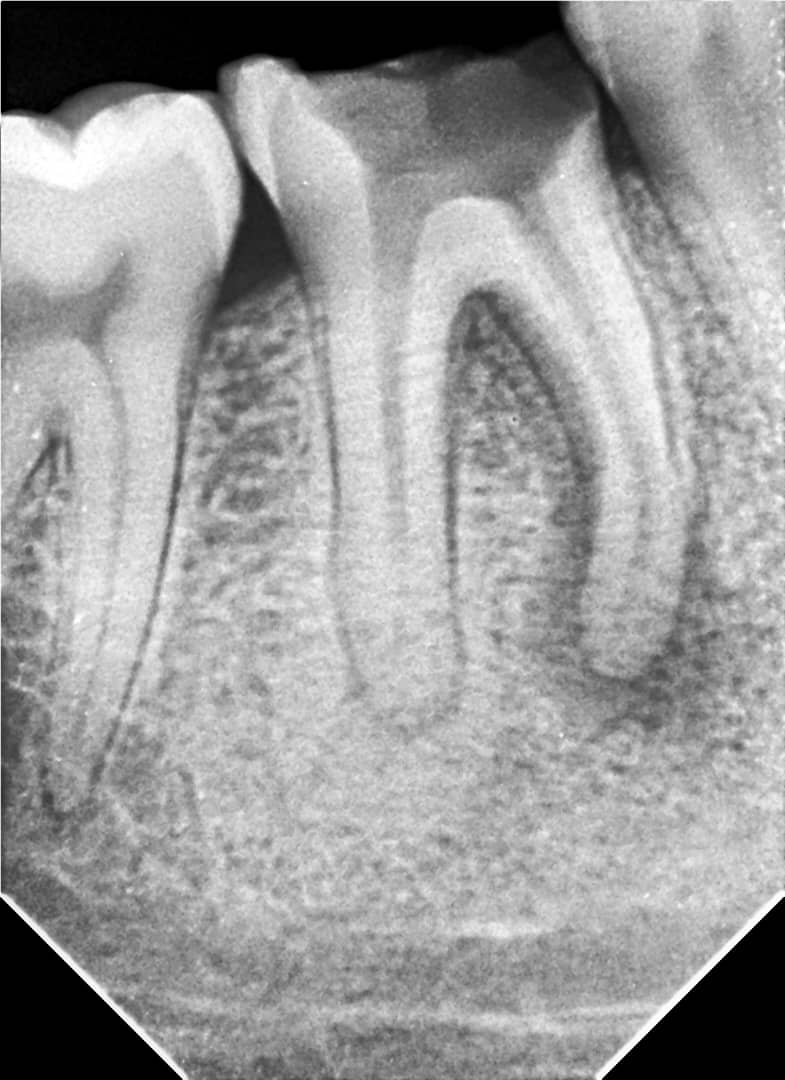

A female patient presented with complaints of severe pain and swelling in the area of tooth #46.

Clinical findings:

- Tooth was severely decayed, cavity filled with softened dentin and food debris

- Percussion was sharply painful

- Thermal test — negative

- Swelling and hyperemia of the mucosa in the vestibular fold area

Diagnosis: Symptomatic Apical Periodontitis of tooth #46